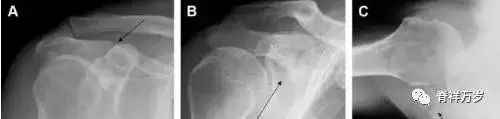

图 5 肩峰骨折。内旋位前后位(A)片上,骨折线几乎被喙突完全遮挡, 但是在标准前后位(B)和腋位(C)片上可见骨折线。